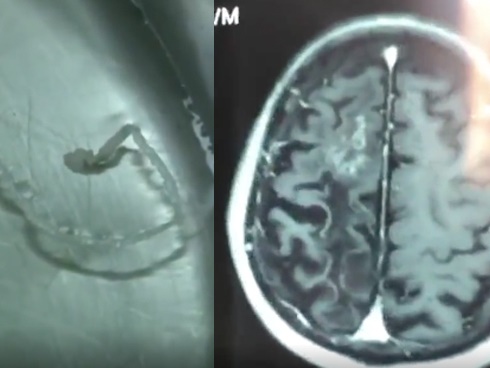

Ngoài nỗi lo về rau nhiễm hóa chất, rau muống còn chứa một loại kí sinh trùng sán lá ruột lớn có tên khoa học là Fasciolopsis Buski. Đây là loại ký sinh trùng thường sống trên các loại rau thủy sinh. Khi xâm nhập vào cơ thể người thông qua con đường ăn uống, chúng có thể gây đau bụng, tiêu chảy hoặc mẩn ngứa, dị ứng đối với người dùng.

Người ăn phải những cây thủy sinh chưa nấu chín sẽ ăn theo cả ấu trùng sán lá vào ruột. Khi vào cơ thể, ấu trùng bám vào ruột non, ký sinh và trưởng thành ở đấy. Thời gian từ lúc ấu trùng vào cơ thể đến khi trưởng thành khoảng 90 ngày. Khi mắc sán, bệnh nhân chỉ bị mệt mỏi, thiếu máu nhẹ, sức khỏe giảm sút… Khi bệnh toàn phát, người bệnh bị đau bụng kèm theo tiêu chảy. Phân lỏng, không có máu, nhưng nhày và có lẫn nhiều thức ăn không tiêu. Bệnh nhân thường đau bụng ở vùng hạ vị, đau kèm theo tiêu chảy và có thể xảy ra những cơn đau dữ dội. Nếu người bệnh có nhiều sán và không được điều trị, bệnh sẽ ngày càng nặng, có thể bị phù nề, tràn dịch ở nhiều nội tạng và chết trong tình trạng suy kiệt. |